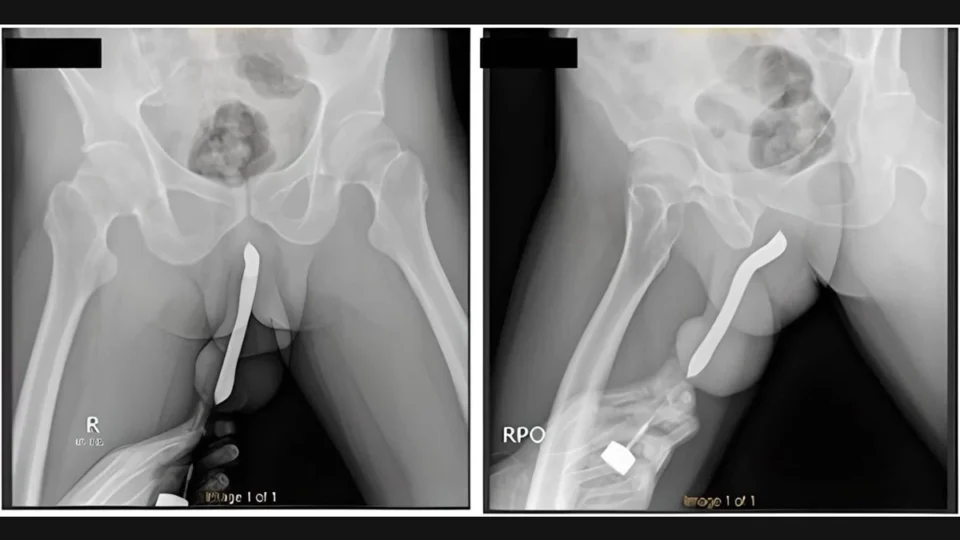

PAÍS | Um homem de 43 anos, da Indonésia, precisou passar por uma cirurgia após uma escova de dentes quebrar dentro do pênis dele durante uma relação sexual. O objeto foi inserido no órgão sexual pelo próprio paciente.

Os médicos do Hospital Geral Acadêmico Soetomo, na cidade de Surabaya, contam que o homem esperou 12 horas para procurar atendimento médico. Ao chegar ao pronto-socorro, o pênis dele estava muito inchado e disforme.

O indonésio passou por uma cirurgia de duas horas e recebeu alta três dias depois. Na consulta de retorno, um mês depois, ele disse não ter sofrido complicações e conseguir urinar normalmente. O pênis também voltou ao formato original.

Foto: Hospital Geral Acadêmico Soetomo/ Divulgação